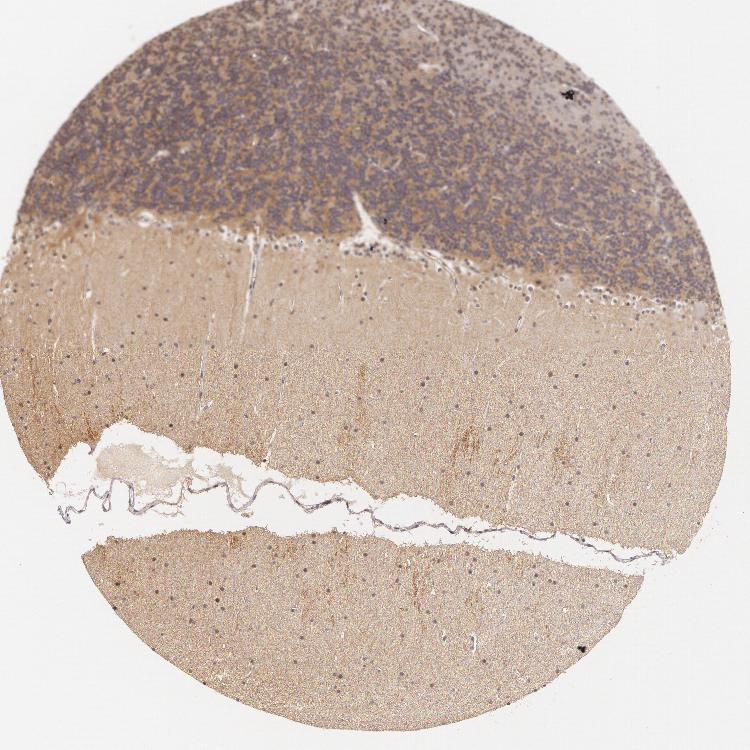

BRAIN CEREBELLUM Show tissue menu

CEREBELLUM - Expression summary

CEREBELLUM - Antibody stainingi

Antibody staining in the annotated cell types in the current human tissue is reported as not detected, low, medium, or high, based on conventional immunohistochemistry profiling in selected tissues. This score is based on the combination of the staining intensity and fraction of stained cells.

Each image is clickable and will lead to virtual microscopy that enables deeper exploration of all samples and also displays staining intensity scores, fraction scores and subcellular localization as well as patient and tissue information for each sample.

Antibody HPA001598Antibody HPA018905

Purkinje cells MediumNot detected

Cells in granular layer MediumLow

Cells in molecular layer LowMedium